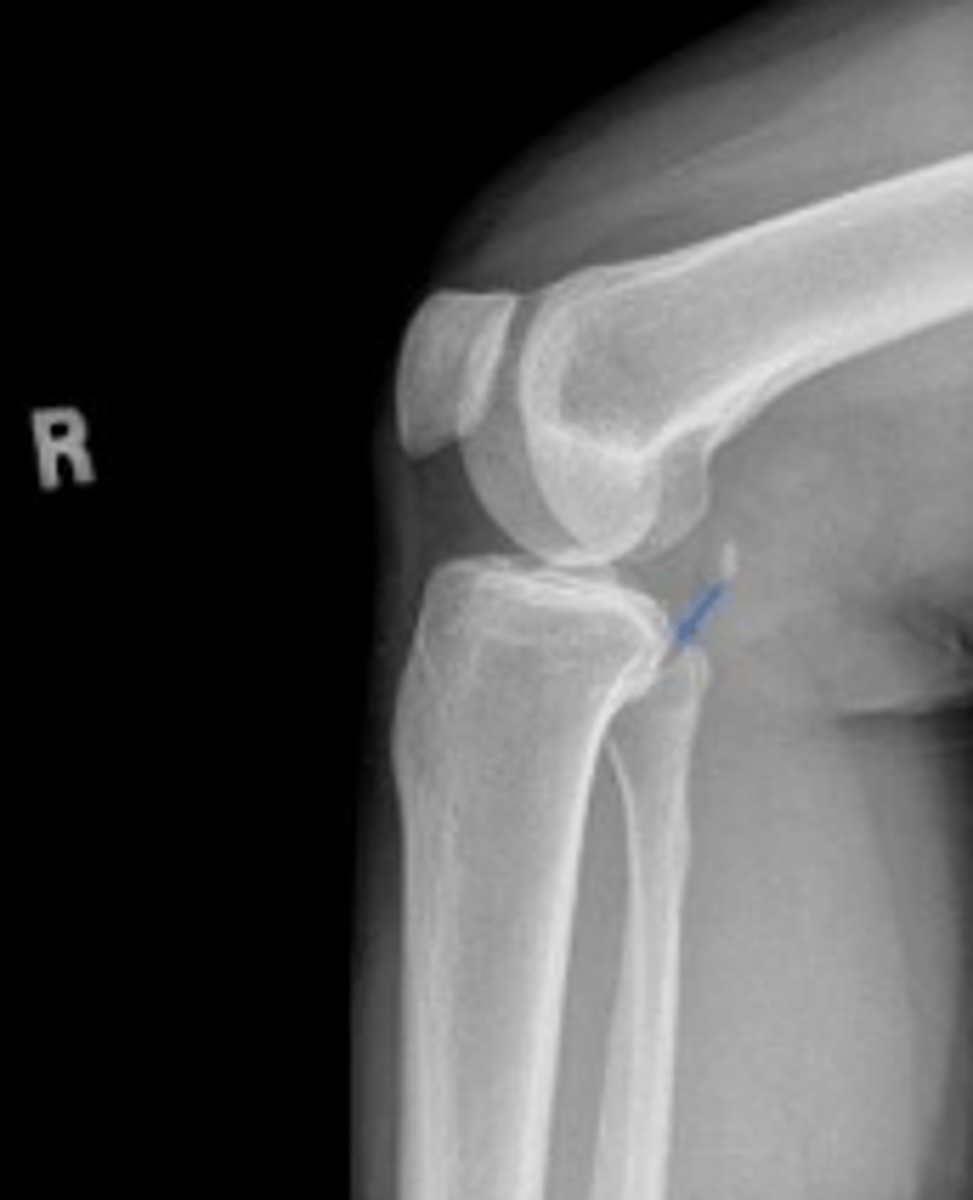

Right lateral knee

What is the name of the radiographic view?

Right patellar ligament

What is outlined?

Right quadriceps tendon

Tuberosity of the right tibia

What area of the tibia is pointed to by the arrows?

Hoffa's fat pad of the right knee

AP knee

Lateral knee

What are the standard radiographic views for the knee (aka minimal diagnostic radiographic series)?